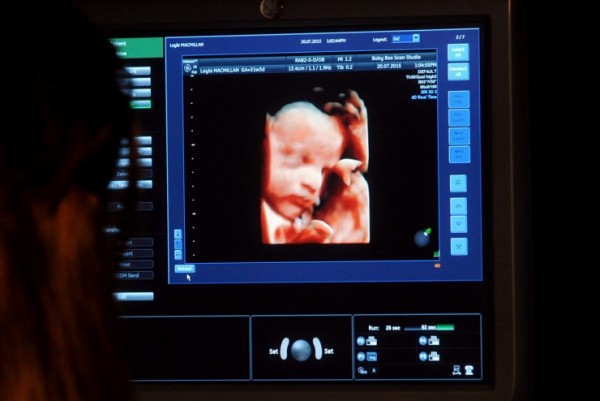

怪异还是美丽?该公司的第一位客户Layla Macmillan的婴儿的扫描

她的第一个客户Layla Macmillan在自己第四次怀孕之后找到了这家公司,而她爱上了这项服务。

特殊时刻:正在Baby:Boo接受扫描的Layla Macmillan

Layla今年28岁,她已经有三个孩子了:七岁的Paige、五岁的Imogen和9个月大的Autumn。她说:“作为一个摄影师,我喜欢这样的事情,我认为这是一个了不起的想法。拥有自己孩子的照片和DVD是一回事,但抱着一个真正的模型非常独特。在你的孩子出生之前就抱着他的脸部塑像,感觉非常特别。怀Autumn时,在29周和31周我们有一个结合扫描。在这个扫描中你能看到孩子的所有特征,你能了解孩子出生后看起来会是什么样。我有Autumn七小时大的照片,她看起来就和结合扫描时一样。”